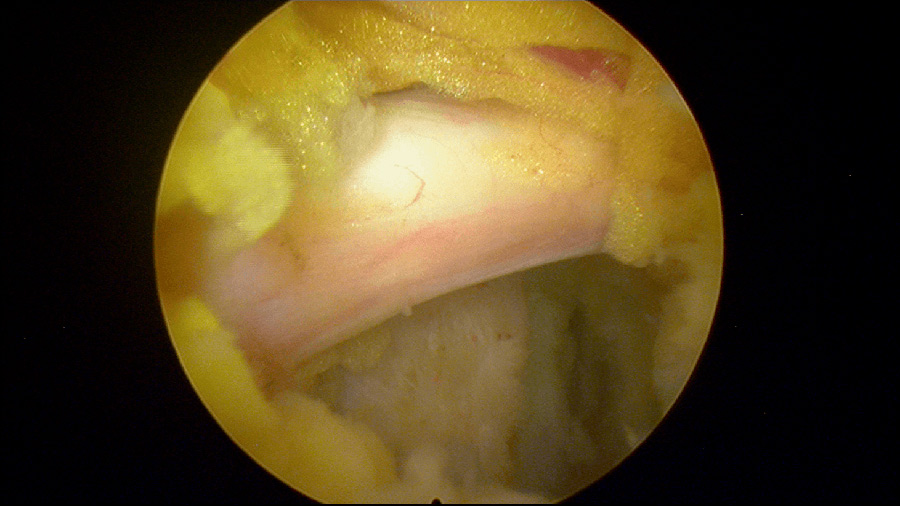

Durante la intervención quirúrgica, se abordarán los dos niveles mediante la técnica de endoscopia de columna.

Mediante una incisión mínima en la piel de 2-3 milímetros, el equipo de ICAC tratará a una paciente joven que sufre una una hernia discal en L4L5 y L5S1.